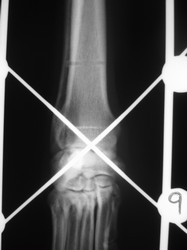

PRÁCTICAS CURSO DE FIJACIÓN EXTERNA PERFECCIONAMIENTO.

Artrodesis carpo.